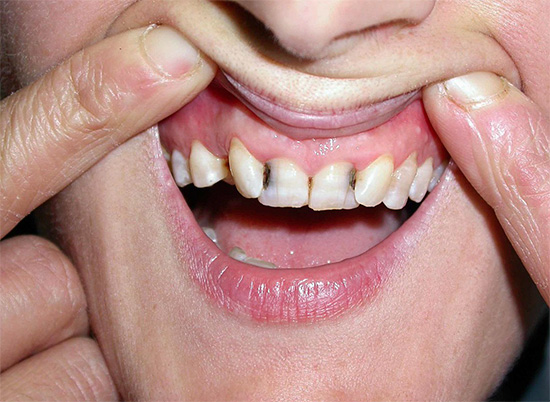

Mas na maioria das vezes os dentes doem devido a várias patologias: devido a cárie profunda, pulpite ou periodontite, e nesses casos a dor pode variar de leve e rápida a muito aguda e constante. Além disso, também pode ser observado inchaço das gengivas e bochechas (edema), febre, dor de cabeça e outros sintomas desagradáveis.

- Cárie, que em diferentes estágios pode se manifestar como dor fraca e que passa rapidamente, e dor bastante forte. Se você suprimir essa dor de dente em casa com pílulas, o processo de cárie inevitavelmente chegará à polpa, resultando em pulpite - e essa é uma dor muito mais intensa, e o tratamento desse dente estará associado à necessidade de remover o "nervo" dele. Geralmente, esse é um procedimento longo e caro, especialmente no caso de dentes multicanais.